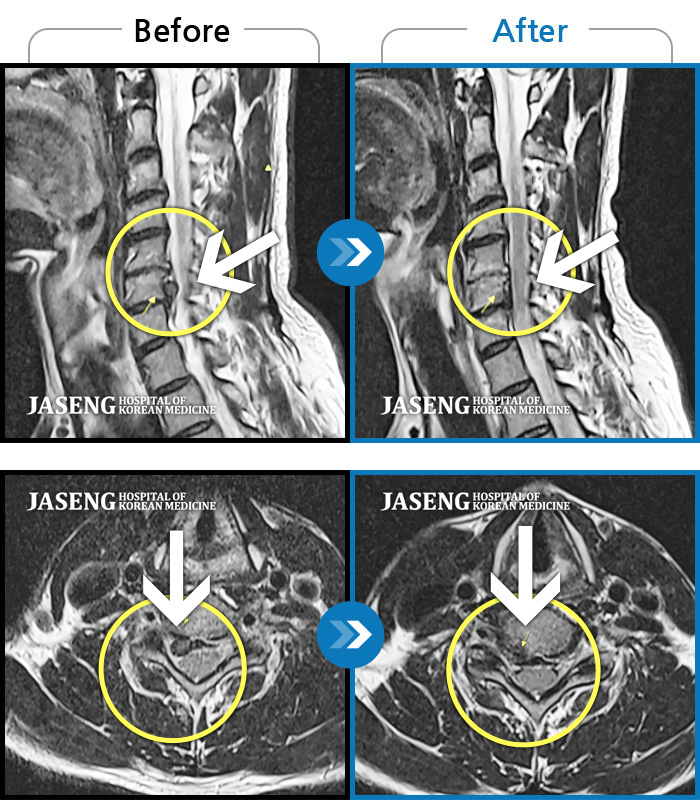

Before

After

환자에게 사전 동의를 받아 동일 조건에서 촬영되었습니다.

개인에 따라 치료 후 부작용이 발생할 수 있으니 의료진과 상담 후 치료를 진행하시기 바랍니다.

급성허리통증으로 내원

우측 허리 골반 하지 방사통